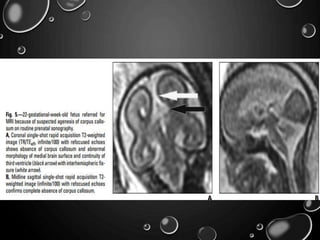

AGENESIS OF THE CORPUS

CALLOSUM

• THE CORPUS CALLOSUM REACHES ADULT FORM BY 18–20

WEEKS’ GESTATION .

• MOST PATIENTS WITH CALLOSAL AGENESIS HAVE

NEURODEVELOPMENTAL DISORDERS, INCLUDING

DEVELOPMENTAL DELAY, MENTAL DISABILITY, AND

EPILEPSY

• OTHER ASSOCIATED -DANDY-WALKER SYNDROME,

CHIARI’S MALFORMATION TYPE II, GRAY MATTER

HETEROTOPIA, HOLOPROSENCEPHALY, SCHIZENCEPHALY,

AND ENCEPHALOCELE.

• FINDINGS OF CALLOSAL AGENESIS—INCLUDING ENLARGED

ATRIA AND OCCIPITAL HORNS WITHA TEARDROP

CONfiGURATION OF THE LATERAL VENTRICLES, ABSENCE

OF THE CAVUM SEPTUM PELLUCIDUM,A HIGH-RIDING

THIRD VENTRICLE, AND RADIATING MEDIAL SULCI—CAN BE

DIFfiCULT TO IDENTIFY SONOGRAPHICALLY.